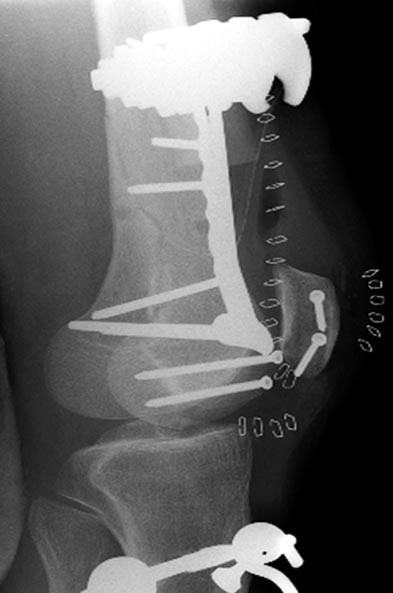

Здесь перечислены ортопедические повреждения: Rt. femoral shaft fracture, Rt femoral head fracture-dislocation, Rt distal femur fracture, Rt. open patella fracture, Rt. talus fracture dislocation, Rt. open humerus fracture, Left 5th metatarsal fracture, Left dislocation 1st TMT.

Раны в области коленного сустава и на плече до сих пор чистые, остаются открытыми. Отсутствует признаки инфекции, решили превратить недостаток в преимущество, т.е. фиксировать через открытые раны пластинами.

На 9й день фиксация дистального бедра, где фрагмент Hoffa и вертикальный перелом надколенника, зафиксированы винтами.

На 11й день фиксация плеча также пластиной.